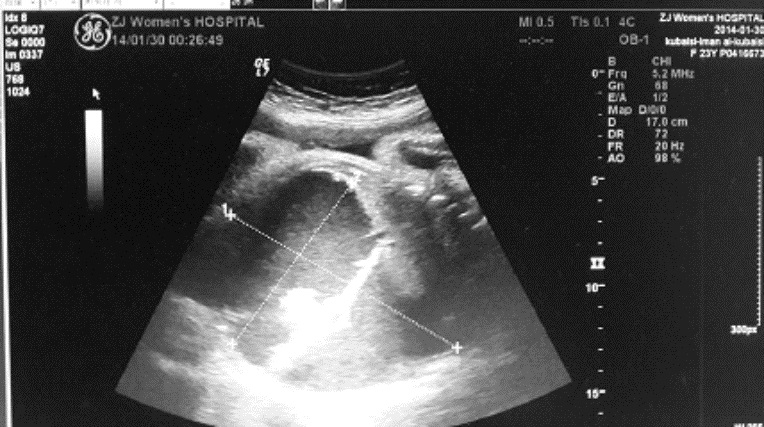

停经37+2周B超示:胎儿腹腔内12.2 cm×9.2 cm×7.2 cm液性暗区,内见分隔样回声,透声差(图 1),同日阴道分娩一男婴,Apgar评分8~9分/1~5 min,体质量2 750 g。新生儿查体:腹胀明显,腹部X线结果:腹部膨隆,两侧膈下无游离气体影,腹腔内中下腹部见不规则团片状及点状稍高密度及高密度影,最大为1.6 cm×1.2 cm,腹内显示少许肠管内有气体,未见明显气-液平面,诊断结果:腹腔囊肿,畸胎瘤?(图 2)。初步诊断:先天性腹腔囊肿,需手术治疗转入浙江大学医学院附属儿童医院。

| 图 1 孕妇产前B超结果 |